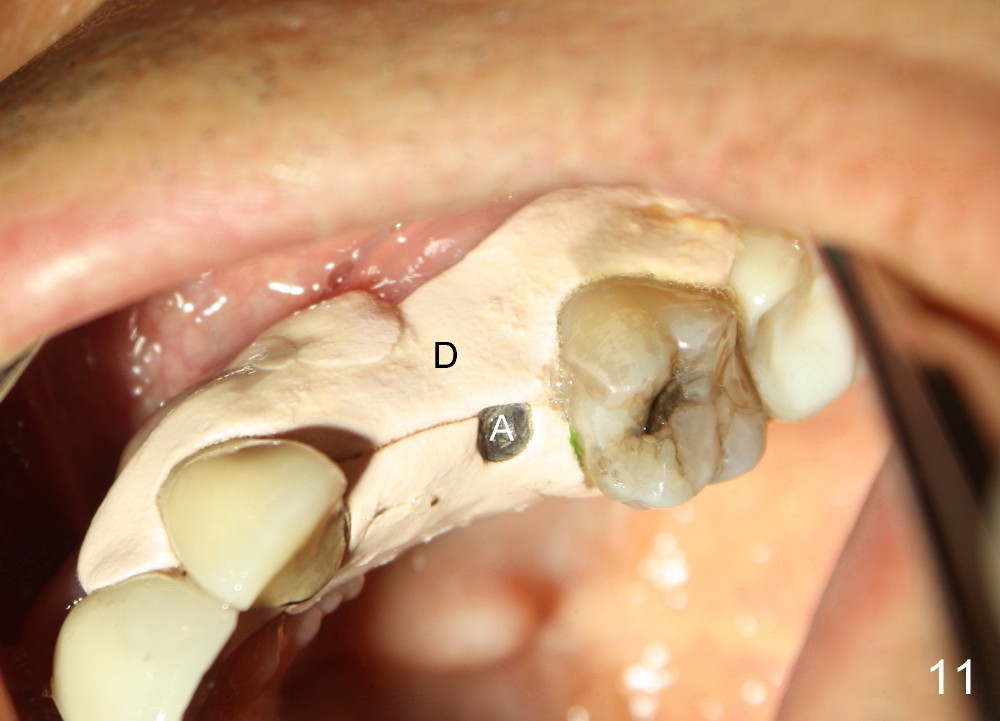

The anterior retainer is kept as a crown at #11 (Fig.2: C), whereas the residual root at the site of #13 is extracted with apical perforation (Fig.3 ^). It is confirmed by Fig.4 (<). To close the perforation, an osteotomy is initiated on the palatal wall of the socket with a 2 mm osteotome (Fig.5 insert: circle). As the osteotomy is being enlarged by a 3 mm osteotome, the bone between the original socket and the osteotomy is being pushed buccally. The former is being closed (Fig.5). The osteotomy is finished with combination of osteotomes and reamers. Fig.6 shows that a 5x14 mm tap is inserted at the site of #13 and that the sinus floor is lifted. In fact the sinus membrane is partially torn at the osteotomy, which is repaired by insertion of Colla-form Dressing (Impladent), followed by autogenous bone (harvested from reamers) mixed with Osteogen (Impladent). A 5x14 mm implant is placed at the site of #13 with insertion torque more than 60 Ncm (Fig.7: I). An incision is made at the site of #12 to start osteotomy with insertion of a parallel pin (Fig.7 P). A 3 mm reamer is kept in place for position confirmation (Fig.8 R). Due to ridge atrophy (Fig.2 arrowheads), a much smaller, but longer implant is placed at the site of #12 (Fig.9: 4x17 mm). The autogenous bone harvested from #12 osteotomy is placed in the buccal gap of #13, followed by insertion of Colla-form Dressing (Fig.10 M). To protect the membrane, a short abutment (4x3 mm) is temporarily placed (Fig.9,10 A) and perio dressing (Fig.9 D) is applied around the abutment and the interproximal areas of the neighboring teeth. Usually perio dressing dislodges around 1 week postop, particularly for a large edentulous space. In this case, the dressing is quite stable 11 days postop: the abutment (Fig.11 A) appears to contribute to retention of the dressing (D).

The perio dressing dislodges 18 days postop (Fig.12). By that time, the extraction wound has healed. The exposed rough surface of the implant (*) is most likely to be covered by fresh and healthy granulation tissue (>) underneath the gingiva. Subsequently the abutment (A) is removed, since it has finished its temporary function.